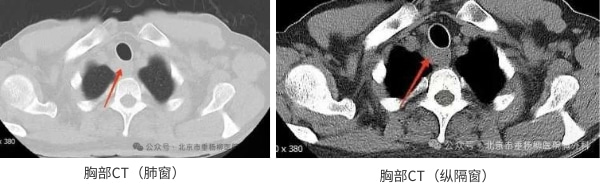

患者男性,60岁,主因“发现纵隔肿物9天余。”来诊。患者自诉9天前因吞咽食物不适感查胸部增强CT,发现上纵隔气管右后方占位,大小约22*24mm,边界欠清,增强扫描不均匀强化,局部气管、食管受累,恶性待排,双肺及纵隔未见肿大淋巴结,未见胸腔积液,后完善胸部增强核磁:上纵隔气管右后方占位不均匀强化,局部气管、食管受累恶性病变待排,必要时穿刺活检;遂于当地医院依次行气管镜、胃镜检查,结果提示:气管上段右后侧壁外压型改变并管腔轻度狭窄;食管管腔通畅,未见异常隆起及异常外压改变,均未取到有效的病理结果。